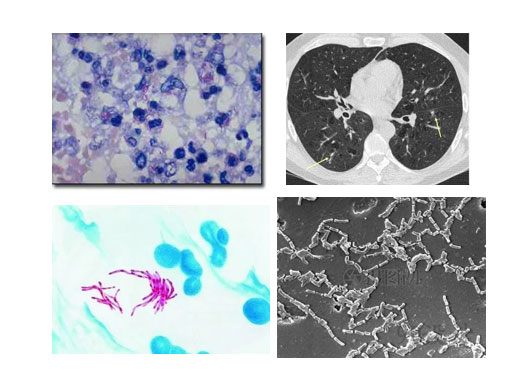

我科也致力于非结核分枝杆菌的诊断与治疗。我们拥有先进的分枝杆菌菌种鉴定技术及NGS技术,能够精确到非结核分枝杆菌菌种,并能够进行体外药敏试验,为患者制定个体化治疗方案。